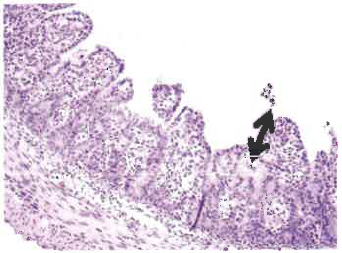

由于丁酸鹽對腸道健康有益,它可有效對抗豬流行腹瀉引起的不良反應 豬流行性腹瀉(PED)是由一種冠狀病毒引起的,該病毒與豬傳染性胃腸炎病毒具有一定相似性。 PED病毒首次于1971年在英國發(fā)現(xiàn),后來大面積擴散到了多個歐洲、亞洲國家,造成流行性傳染。 圖1. PED的典型癥狀:仔豬嘔吐、腹瀉、消瘦 圖2. 急性病毒性腹瀉的典型癥狀:嚴重脫水、死亡 歐洲很少爆發(fā)高死亡率的嚴重疫情,但最近亞洲頻繁出現(xiàn)了有關疫情的報告。由于新毒株的出現(xiàn),自2010年以來中國的爆發(fā)率大幅升高,美國直到2013年春才爆發(fā)疫情,這首次驗證了PED病毒的出現(xiàn)。 與此同時,加拿大也發(fā)現(xiàn)了該病毒,美國有27個州都發(fā)生了一例以上PED確診病例。近日,哥倫比亞和日本也可能出現(xiàn)了此病毒。 預防和治療 預防傳染的關鍵仍是確保良好的生物安全。但對于PED這樣的高傳染性疾病,維持生物安全并非易事。之前已經(jīng)過病毒暴露并獲得免疫的母豬,可通過初乳將抗體傳給新生仔豬,使之在4-13日齡前獲得對經(jīng)口感染病毒的免疫保護。目前,只有韓國、日本和中國有批準生產(chǎn)的PED疫苗。給經(jīng)產(chǎn)母豬和后備母豬飼喂帶有病毒的小腸內(nèi)容物或糞便也可激發(fā)免疫,但迄今為止,此種免疫不能持續(xù)長久,仍有復發(fā)的風險。此外,根據(jù)地方立法,使用此方法可能會觸犯法律,因為傳播污染物可導致疾病進一步擴散。 圖3. 正常新生仔豬的小腸絨毛腸絨毛(黑色箭頭處)較長,具有很大的表面積,以便吸收營養(yǎng)和水分。隱窩(黑色圓圈處)中有新細胞產(chǎn)生。 目前,治療方法主要為輔助性對癥治療:預防脫水(補充電解質(zhì),保持體溫),防止繼發(fā)性感染。 丁酸鹽的潛在用途 除以上治療方法外,業(yè)界還在尋求其他防治手段,以增強動物免疫抵抗力,促進豬的迅速痊愈。丁酸鹽對于腸道細胞生長以及腸道健康具有特殊功效,是一種不錯的選擇。研究表明,丁酸鹽不僅可為上皮細胞系統(tǒng)提供能量,而且能顯著促進小腸上皮細胞增殖、分化及成熟,還可改善結(jié)腸的屏障功能。 丁酸鹽可影響基因表達和蛋白合成,從而加速腸粘膜的發(fā)育、成熟和損傷修復。丁酸鹽的保護和修復作用已通過活體微生物攻毒試驗證實(以大腸桿菌感染仔豬,產(chǎn)氣莢膜梭菌感染家禽,導致細菌像PED病毒一樣破壞腸道屏障)。在攻毒試驗中,飼喂丁酸鹽能顯著減輕了PED對腸道的不良影響,使受感染的動物的生長率水平接近于受感染的動物。此外,丁酸鹽可調(diào)節(jié)離子吸收,有助于緩解腹瀉。 大量文獻以及養(yǎng)殖經(jīng)驗均顯示,丁酸鹽對幼仔腸道發(fā)育的作用尤其顯著。研究表明,丁酸鹽可改善新生仔豬和斷奶仔豬的生長性能,給仔豬越早飼喂丁酸鹽,效果越好。這一特性對易受PED疾病威脅的幼崽非常有幫助。 圖4. 腸絨毛急劇縮短(絨毛萎縮,見黑色箭頭處)、感染PED病毒約36小時后喪失上皮吸收功能的新生仔豬隱窩變長,以便形成更多細胞,修復絨毛上皮細胞的吸收功能。 臺灣大學的研究人員最近考察了感染PED后新生仔豬的存活率。他們將出生一周的仔豬與母豬分離,施加干預,并進行了存活率的比較。對照組僅有20%感染仔豬存活到第二周,而間歇給予添加了1.5kg/T Adimix 30 Coated的液體飼料的試驗組中則有70%存活。以上結(jié)果證明,補充Adimix可使仔豬更好的對抗PED感染,提高存活率。 圖5.基質(zhì)包被丁酸鈉(Adimix 30 Coated)可確保精確輸送 圖6.高質(zhì)量包衣的重要性 選擇正確的產(chǎn)品 由于病毒可破壞小腸和結(jié)腸細胞,因此丁酸鹽能夠達到這些區(qū)域是至關重要的。理想狀況是讓丁酸鹽僅到達腸道的管腔下部,避免在胃中代謝,并在腸道遠端緩慢釋放。利用準確定量輸送系統(tǒng),如Adimix 30 Coated,是實現(xiàn)丁酸鹽靶向緩釋的最有效的方式。 市場上多種包膜丁酸鹽產(chǎn)品可適用于動物生產(chǎn)。這些產(chǎn)品類型各異,使用時應明辨良莠。高質(zhì)量包衣可實現(xiàn)丁酸鹽的精確輸,而普通包衣僅能遮住丁酸鹽的氣味。 最近,伊利諾斯大學的一項研究證明了高質(zhì)量包衣的重要性。斷奶仔豬被隨機分為3個日糧處理組(每個處理6個重復)。 1.基礎飼糧 2.基礎飼糧+4kg/T 遮味包膜丁酸鹽(50% 丁酸鈉) 3.基礎飼糧+4kg/T 精確輸送丁酸鹽(Adimix 30 Coated,30%丁酸鈉) 將豬安樂處死,在腸道各個部位進行取樣分析,確定丁酸鹽濃度。與對照組(1)以及遮味包膜組(2)相比,飼喂Adimix 30 Coated的斷奶仔豬的空腸和回腸中含有較高濃度丁酸鹽,且差異顯著(P< 0.05)。由此說明,即便在添加較低濃度(30%)的丁酸鈉時,高質(zhì)量包膜(Adimix 30 Coated)仍能將丁酸鈉準確輸送到豬腸道下端,而添加較高濃度(50%)但缺乏保護的遮味包膜卻不能做到這一點。 摘要 鑒于其對腸道健康具有諸多益處,丁酸鹽可有效防治豬流行性腹瀉。 確保丁酸鹽的靶向釋放是發(fā)揮丁酸鹽效能的關鍵。由于市場上包膜的效能差異懸殊,在動物生產(chǎn)中明確鑒別和應用高質(zhì)量包膜對于有效利用丁酸鹽至關重要。我們的試驗結(jié)果,表明 Adimix 30 Coated可將丁酸鹽輸送到受PED感染最嚴重的部位。 作者:Maja Marien, 獸醫(yī)學博士、理學博士(m.marien@nutriad.com) Tim Goossens,理學博士、比利時Nutriad 消化性能部產(chǎn)品經(jīng)理(t,goossens@nutriad.com) 來源:國際畜牧網(wǎng)-Nutriad |